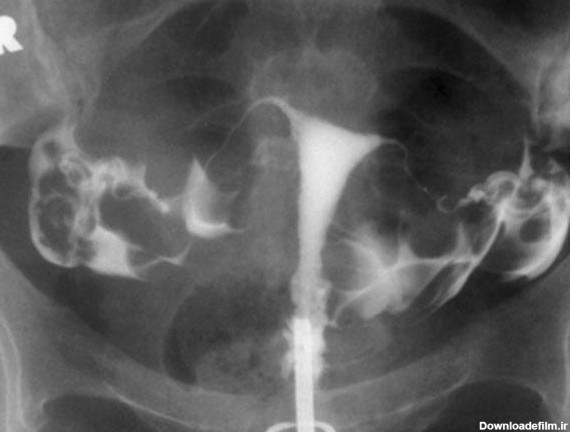

عکس رنگی رحم یا هیستروسالپنگوگرافی روشی است که به منظور بررسی داخل رحم و لوله های رحمی انجام می گیرد و انجام آن در ارزیابی ناباروری بسیار مهم است.